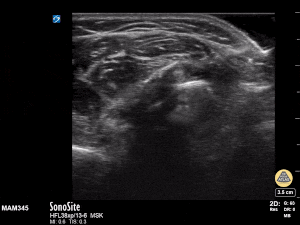

11y female with L BB forearm fx from fall during gym class. Long axis view with clear discontinuity of proximal and distal components of the shaft. Transverse view with transition from single bony cortex to overlap of fracture ends. Matthew Moake, MD PhD